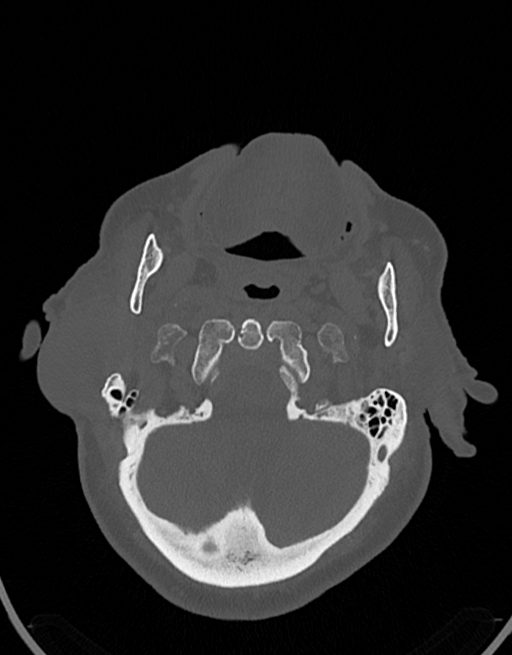

در سی تی اسکن ادنوم پاروتید، دستگاه تصاویری عرضی مقطع ایی از گوش در ناحیه سر و صروت ایجاد می کند. این تصویربرداری از اشعه ایکس برای ایجاد تصویر استفاده می کند.

در سي تي اسکن اسپيرال نازو فارنکس با و بدون کنتراست (مولتي ديدکتور 16 با مقاطع ظريف و بازسازي هاي ساژيتال و کرونال):

– توده نسج نرمي به ابعاد mm 40 x 45 x 60 در ناحيه پاروتيد راست، با enhancement هتروژن پس از تزريق کنتراست مشهود است که مطرح کننده آدنوم پاروتيد مي باشد.

– شواهدي از تهاجم توده به استخوان و عروق اطراف مشهود نيست .

– کلسيفيکاسيون در ديواره شريان هاي کاروتيد دو طرف مشهود است .